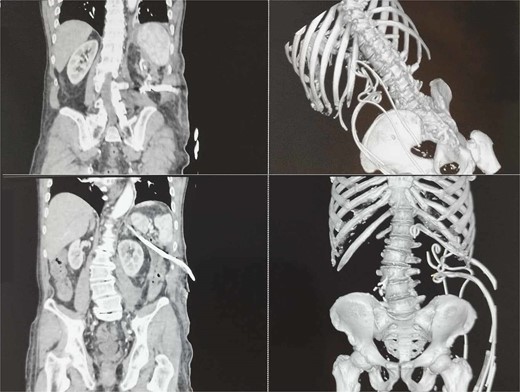

Nine days later, a persistent fever reaching 38.6°C with tenderness in upper abdominal quadrants was presented. In addition, the patient reported significant fatigue and exhibited tachycardia with a heart rate of up to 106 beats per minute. Laboratory findings revealed leukocytosis (15.03 G/L) with neutrophilia (11.84 G/L), moderately elevated serum amylase (394 U/L), and hyperbilirubinemia (total – 31.7 μmol/L, direct – 23.1 μmol/L). Abdominal ultrasound showed an enlarged pancreas with blurred, heterogeneous hypoechoic echostructure, indistinct gland margin, peripancreatic fluid, and walled-off necrosis next to the pancreatic tail, extending laterally to the splenorenal recess, with a longitudinal size of ~10 cm and thick heterogeneous content, suggesting secondary inflammation. Computed tomography (CT) verified gas-containing fluid collections spreading from the pancreas to the left iliac crest (Fig. 1A and B) along with bilateral pleural effusions.

CT image of large infected peripancreatic collections with multiple air locules (A and B) and placed pigtail catheters post-imaging (C and D).

Following well-established guidelines, empiric antibiotic therapy with a carbapenem was started (Meropenem 1 g every 8 hours). The patient underwent PCD with the initial insertion of five drains: two in the peripancreatic collection and three in the pararenal space, with one situated caudal to the lower border of the collection at the level of the iliac crest. Microbiological examination revealed the presence of Meropenem-resistant Escherichia coli, sensitive to Cefoperazone-sulbactam, necessitating a change in antibiotic treatment according to antibiogram results. Continuous postprocedural transcatheter lavage with physiological saline was performed. Follow-up abdominal sonography showed the persistence of a small undrained collection in the posterior pararenal space, leading to the placement of two additional drains in that area (Fig. 1C and D).